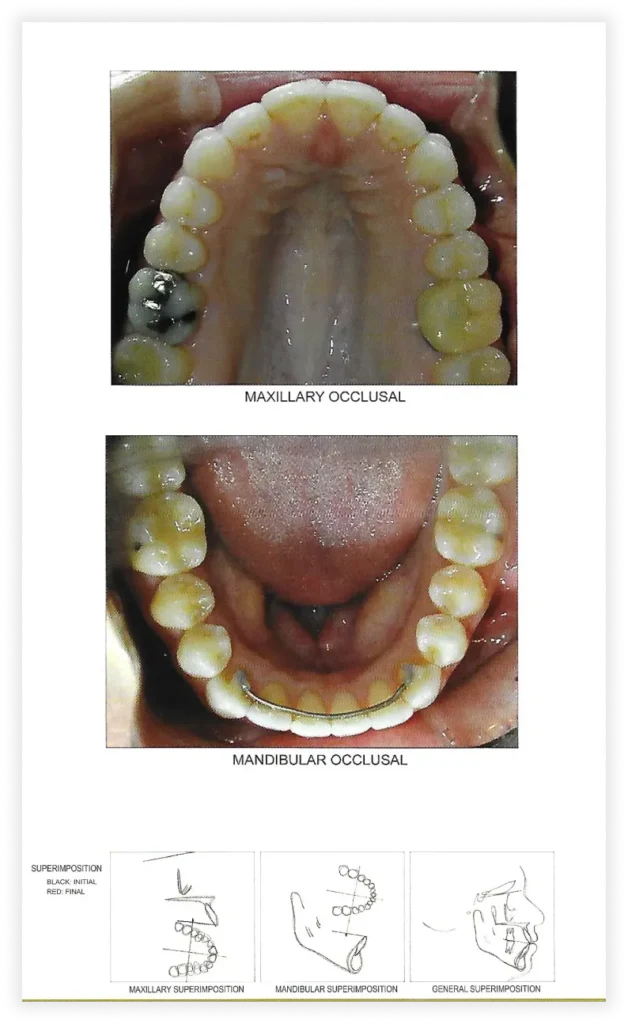

Final Photos